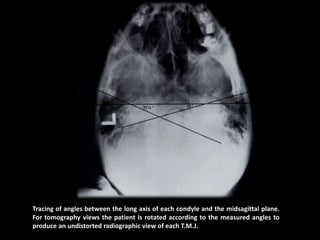

Tracing of angles between the long axis of each condyle and the midsagittal plane.

For tomography views the patient is rotated according to the measured angles to

produce an undistorted radiographic view of each T.M.J.